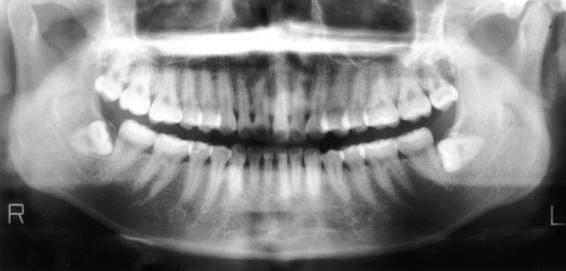

さて次のレントゲンをご覧下さい。

親知らずの手前の7番目の歯、上に飛び出てますよね。

グイグイグイと「どけどけどけ!」と。

いまだにこの「親知らず」活発です。

このままほっといても7番目は抜けてしまいます。

「親知らず」が原因で7番目の歯が勝手に抜けちゃうわけです。

飛び出て行っちゃいます。

このレントゲン写真をご覧下さい。

スポーツをされている方です。

こういう症例は実は本当に難しいんです。

この写真を見ると、ほとんどきれいな歯なんです。

白く光る部分がほとんどありません。

ところが、1本だけ、2本だけ、歯科治療をされていました。

そして、この歯は根っこの治療までされています。

ほとんど虫歯なんかない。

治療なんかしたことすらない。

でも必ずいつも同じ歯が何度も悪くなる。

左上の歯は神経まで治療されています。